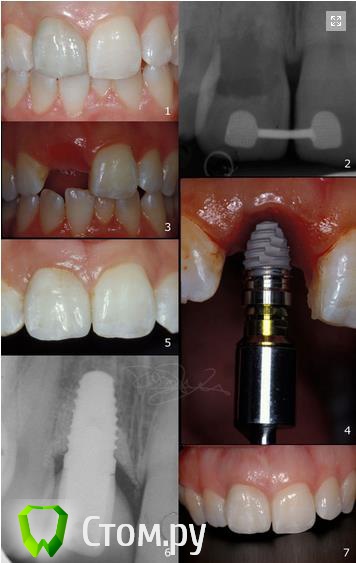

Olga1001 Опубликовано 7 февраля, 2014 Поделиться Опубликовано 7 февраля, 2014 http://avosdent.ru/userfiles/images/top.png Дорогие коллеги! Приглашаем Вас посетить однодневный лекционно-практический курс 25 апреля, посвященный современным методам костной и тканевой регенерации. Курс проведет известный итальянский хирург – доктор Роберто Росси. Курс рекомендован продвинутым хирургам-имплантологам и пародонтологам. В рамках мероприятия доктор Росси прочитает лекции на актуальные темы, проведет мастер-классы и обсуждения с аудиторией. Участников ожидает увлекательная образовательная программа, практические работы с индивидуальным подходом и благоприятная обстановка на протяжении всего мероприятия. Ощущение комфортной атмосферы подарит конференц-зал с панорамным видом на центр столицы, богатый ассортимент блюд на обед и, безусловно, приятная компания коллег. Слушателям будет предоставлен синхронный перевод на русский язык. Темы курса:Методики восстановления кости вокруг зубов;Сохранение гребня;Управление свежими лунками;Регенерация кости и одновременная установка имплантата;Поздние осложнения периимплантита;Дегисценции и рецессии;Горизонтальное увеличение атрофичного гребня;Увеличение объема мягких тканей;Малоинвазивные техники регенерации мягких тканей при помощи свиных дерм и пр. Программа9.00-9.15 – Вступление9.15-11.00 – Пародонтальная регенерация11.00-11.15 – Кофе-брейк 11.15-13.00 – Альвеолярная регенерация: сохранение лунки и гребня13.00-13.45 – Обед13.45-14.45 – Лечение периимплантита14.45-15.45 – Реконструкция при атрофии гребня15.45-16.45 – Увеличение объема мягких тканей16.45-17.00 – Обсуждения, вопросы и ответы17.00-17.15 – Кофе-брейк17.15-19.00 – Мастер классы с использованием моделей пластиковых челюстейТемы мастер-класса:Лечение внутрикостных дефектов с костными материалами и рассасывающимися мембранами;Лечение дефектов альвеолярного гребня при помощи кортикальной пластины и гетерологичной кортикально-губчатой костной смеси. http://avosdent.ru/userfiles/images/rossi_biography.pngСмотрите клинические случаи от доктора Роберто Росси в прикрепленных файлахУсловия и регистрация участия Стоимость посещения лекции и мастер-класса для участников форума stom.ru: 10 000 рублейВ стоимость включены: лекции, мастер-класс, синхронный перевод, кофе-брейки, обед.Максимальное количество участников: 35 человек Способы регистрацииПо электронной почте olga@avosdent.ru, посредством личных сообщений или онлайн формы (прием заявок круглосуточно, промо-код для получения специальной цены: STOM.RU)По телефону +7 (495) 739 50-24 (прием заявок пн-пт, 9.00-17.00)Гарантией участия является полная и своевременная оплата. Мы также рады предложить специальные условия проживания для гостей столицы. Мероприятие организовано компанией Avos Dent при поддержке Tecnoss Dental, производителя остеопластических материалов OsteoBiol. http://avosdent.ru/userfiles/images/bottom.png 1 Ссылка на комментарий